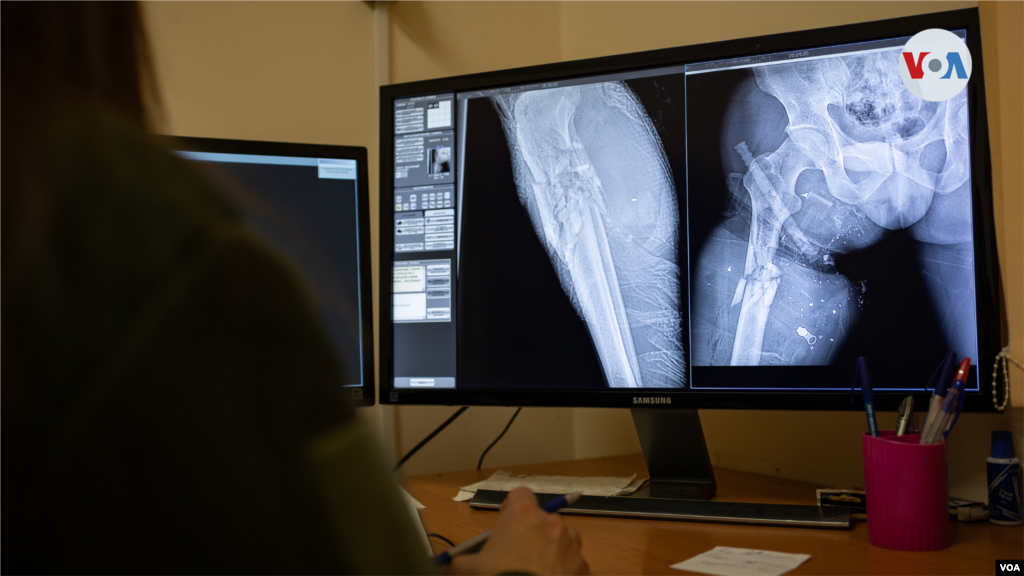

Radiografía de un soldado ucraniano herido por metralla. En la imagen se puede ver el torniquete de aplicación de combate en la pierna izquierda.